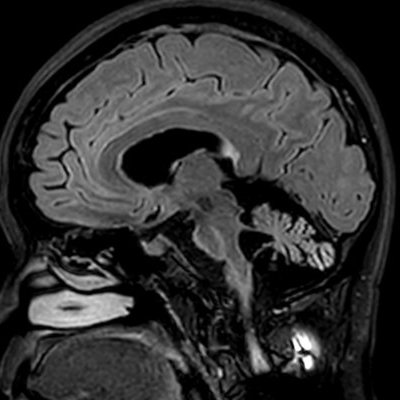

Фотобиомодуляция — неинвазивный метод светотерапии низкой интенсивности, может улучшить умственные функции, смягчая негативное воздействие хронического стресса. Исследование на мышах выявило, что такая терапия способствует восстановлению молекулярного пути SIRT1, который связан со старением и потерей нервных клеток.

Фотобиомодуляция также изменяет работу кишечных бактерий, что ведет к снижению воспаления в головном мозге и улучшению психического здоровья. Это открытие подчеркивает важность интегрированных подходов в лечении психических расстройств, включая возможное сочетание светотерапии с традиционной фармакотерапией в случаях тяжелой депрессии, сообщает Газета.Ру.

Фото: commons.wikimedia.org/Argarrett (Creative Commons Attribution-Share Alike 4.0 International license)